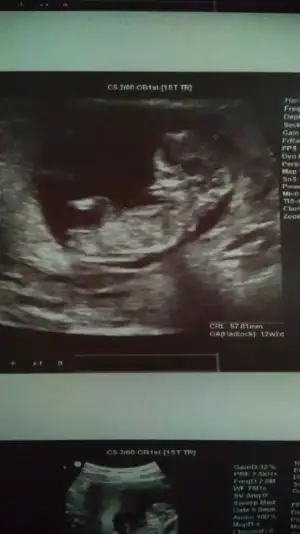

13 haftalık :) doktor söylemedi cinsiyetini yanıltıcı olabilir dedi. Tahmini ni bile söylemediKaç haftalık sanki kız gibi 12 hafta paylaşın

Başka usg varmı teyit edim13 haftalık :) doktor söylemedi cinsiyetini yanıltıcı olabilir dedi. Tahmini ni bile söylemedi. Teşekkür ederim